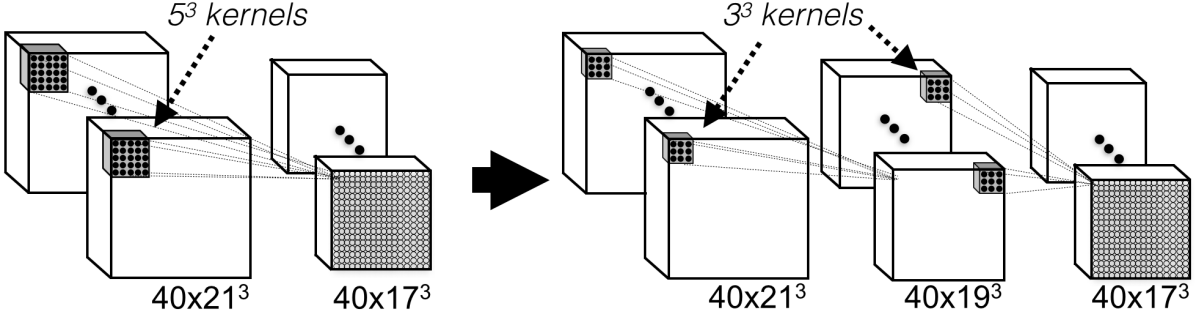

In order to build a deeper 3D architecture, we adopt the sole use of small kernels that are faster to convolve with and contain less weights. This design approach was previously found beneficial for classification of natural images (Simonyan and Zisserman (2014)) but its effect is even more drastic on 3D networks. When compared to common kernel choices of (Zikic et al. (2014); Urban et al. (2014); Prasoon et al. (2013)) and in our baseline CNN, the smaller kernels reduce the element-wise multiplications by a factor of approximately while reducing the number of trainable parameters by the same factor. Thus deeper network variants that are implicitly regularised and more efficient can be designed by simply replacing each layer of common architectures with more layers that use smaller kernels (Fig. 4).

The 5-layers baseline CNN (Fig. 2), here referred to as the “Shallow” model, is extended to 9-layers by replacing each convolutional layer that uses kernels with two layers that use kernels (Fig. 4). This model is referred to as “Deep”. Training the latter, however, utterly fails with the model making only predictions corresponding to the background class. This problem is related to the challenge of preserving the signal as it propagates through deep networks and its variance gets multiplied with the variance of the weights, as previously discussed in Sec. 2.3. One of the causes is that the weights of both models have been initialized with the commonly used scheme of sampling from the normal distribution (cf. Krizhevsky et al. (2012)). In comparison, the initialization scheme by He et al. (2015), derived for preserving the signal in the initial stage of training, results in higher values and overcomes this problem. Further preservation of the signal is obtained by employing Batch Normalization. This results in an enhanced 9-layers model which we refer to as “Deep+”, and using the same enhancements on the Shallow model yields “Shallow+”. The significant performance improvement of Deep+ over Shallow+, as shown in Fig. 7, is the result of the greater representational power of the deeper network. The two models need similar computational times, which highlights the benefits of utilizing small kernels in the design of 3D CNNs. Although the deeper model requires more sequential (layer by layer) computations on the GPU, those are faster due to the smaller kernel size.